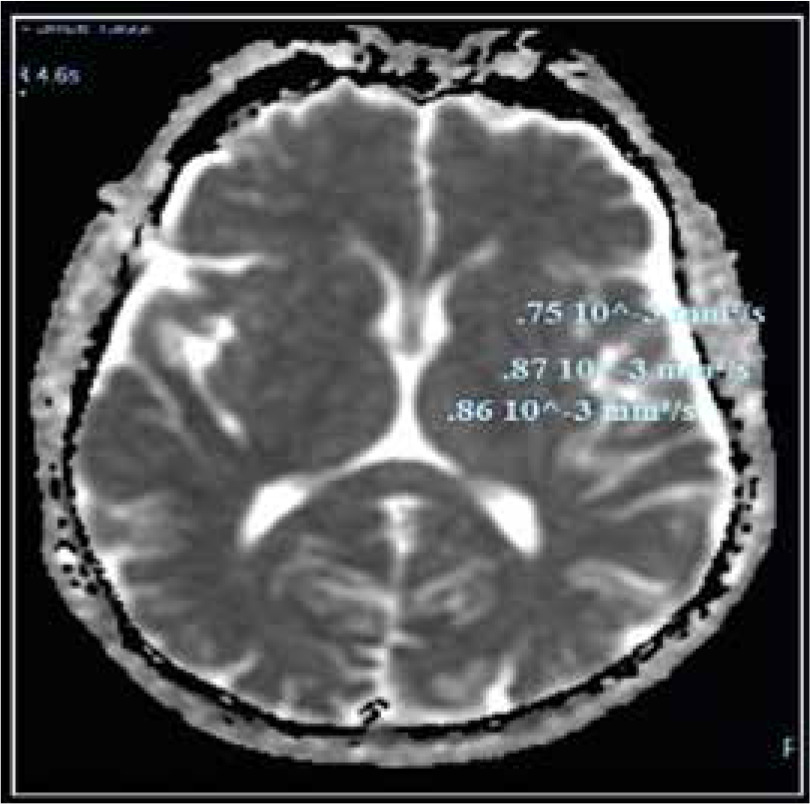

Compared to the control group, the ADC values of cirrhotic patients with HE were significantly higher. There were no significant differences between cirrhotic patients with MHE and those with overt HE in different brain regions. As shown in Table 5 and Figures 3 and 4, there was no statistically significant difference in ADC values between brain regions.

Fig. 3

Apparent diffusion coefficient (ADC) values in different brain regions of a patient with cirrhosis and minimal hepatic encephalopathy (MHE)